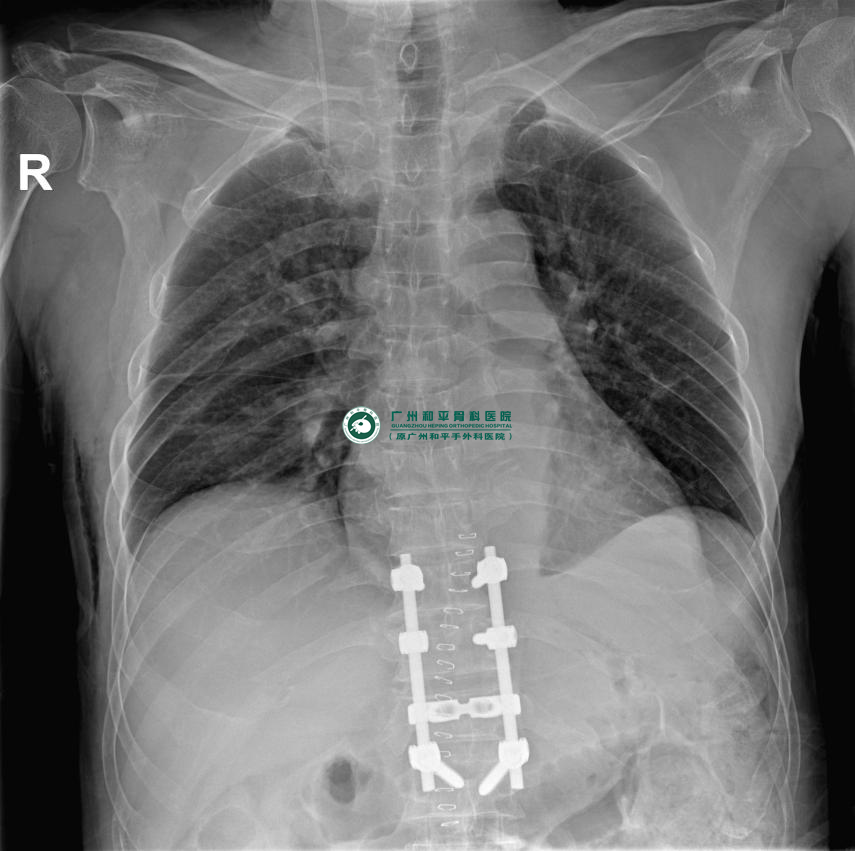

5月6日,该院骨科主任胡铁山、医生王亮和覃光顶为陈先生做脊椎骨折复位内固定、椎管减压术,术中复位骨折块,手术过程很顺利。

脊椎骨折复位内固定

近一周以来,陈先生感觉好多了,腰部、胸痛、双侧髋部疼痛较为减轻,口唇红润,也没有呼吸困难现象,病情已经稳定下来,术后右下肢感觉恢复,运动部分有恢复。陈先生现在的食欲还不错,睡眠和精神良好,家里人看着陈先生慢慢恢复,精神越来越好。陈先生感叹,高空作业不可掉以轻心。看起来7、8米不高,摔下来差点就没命了。